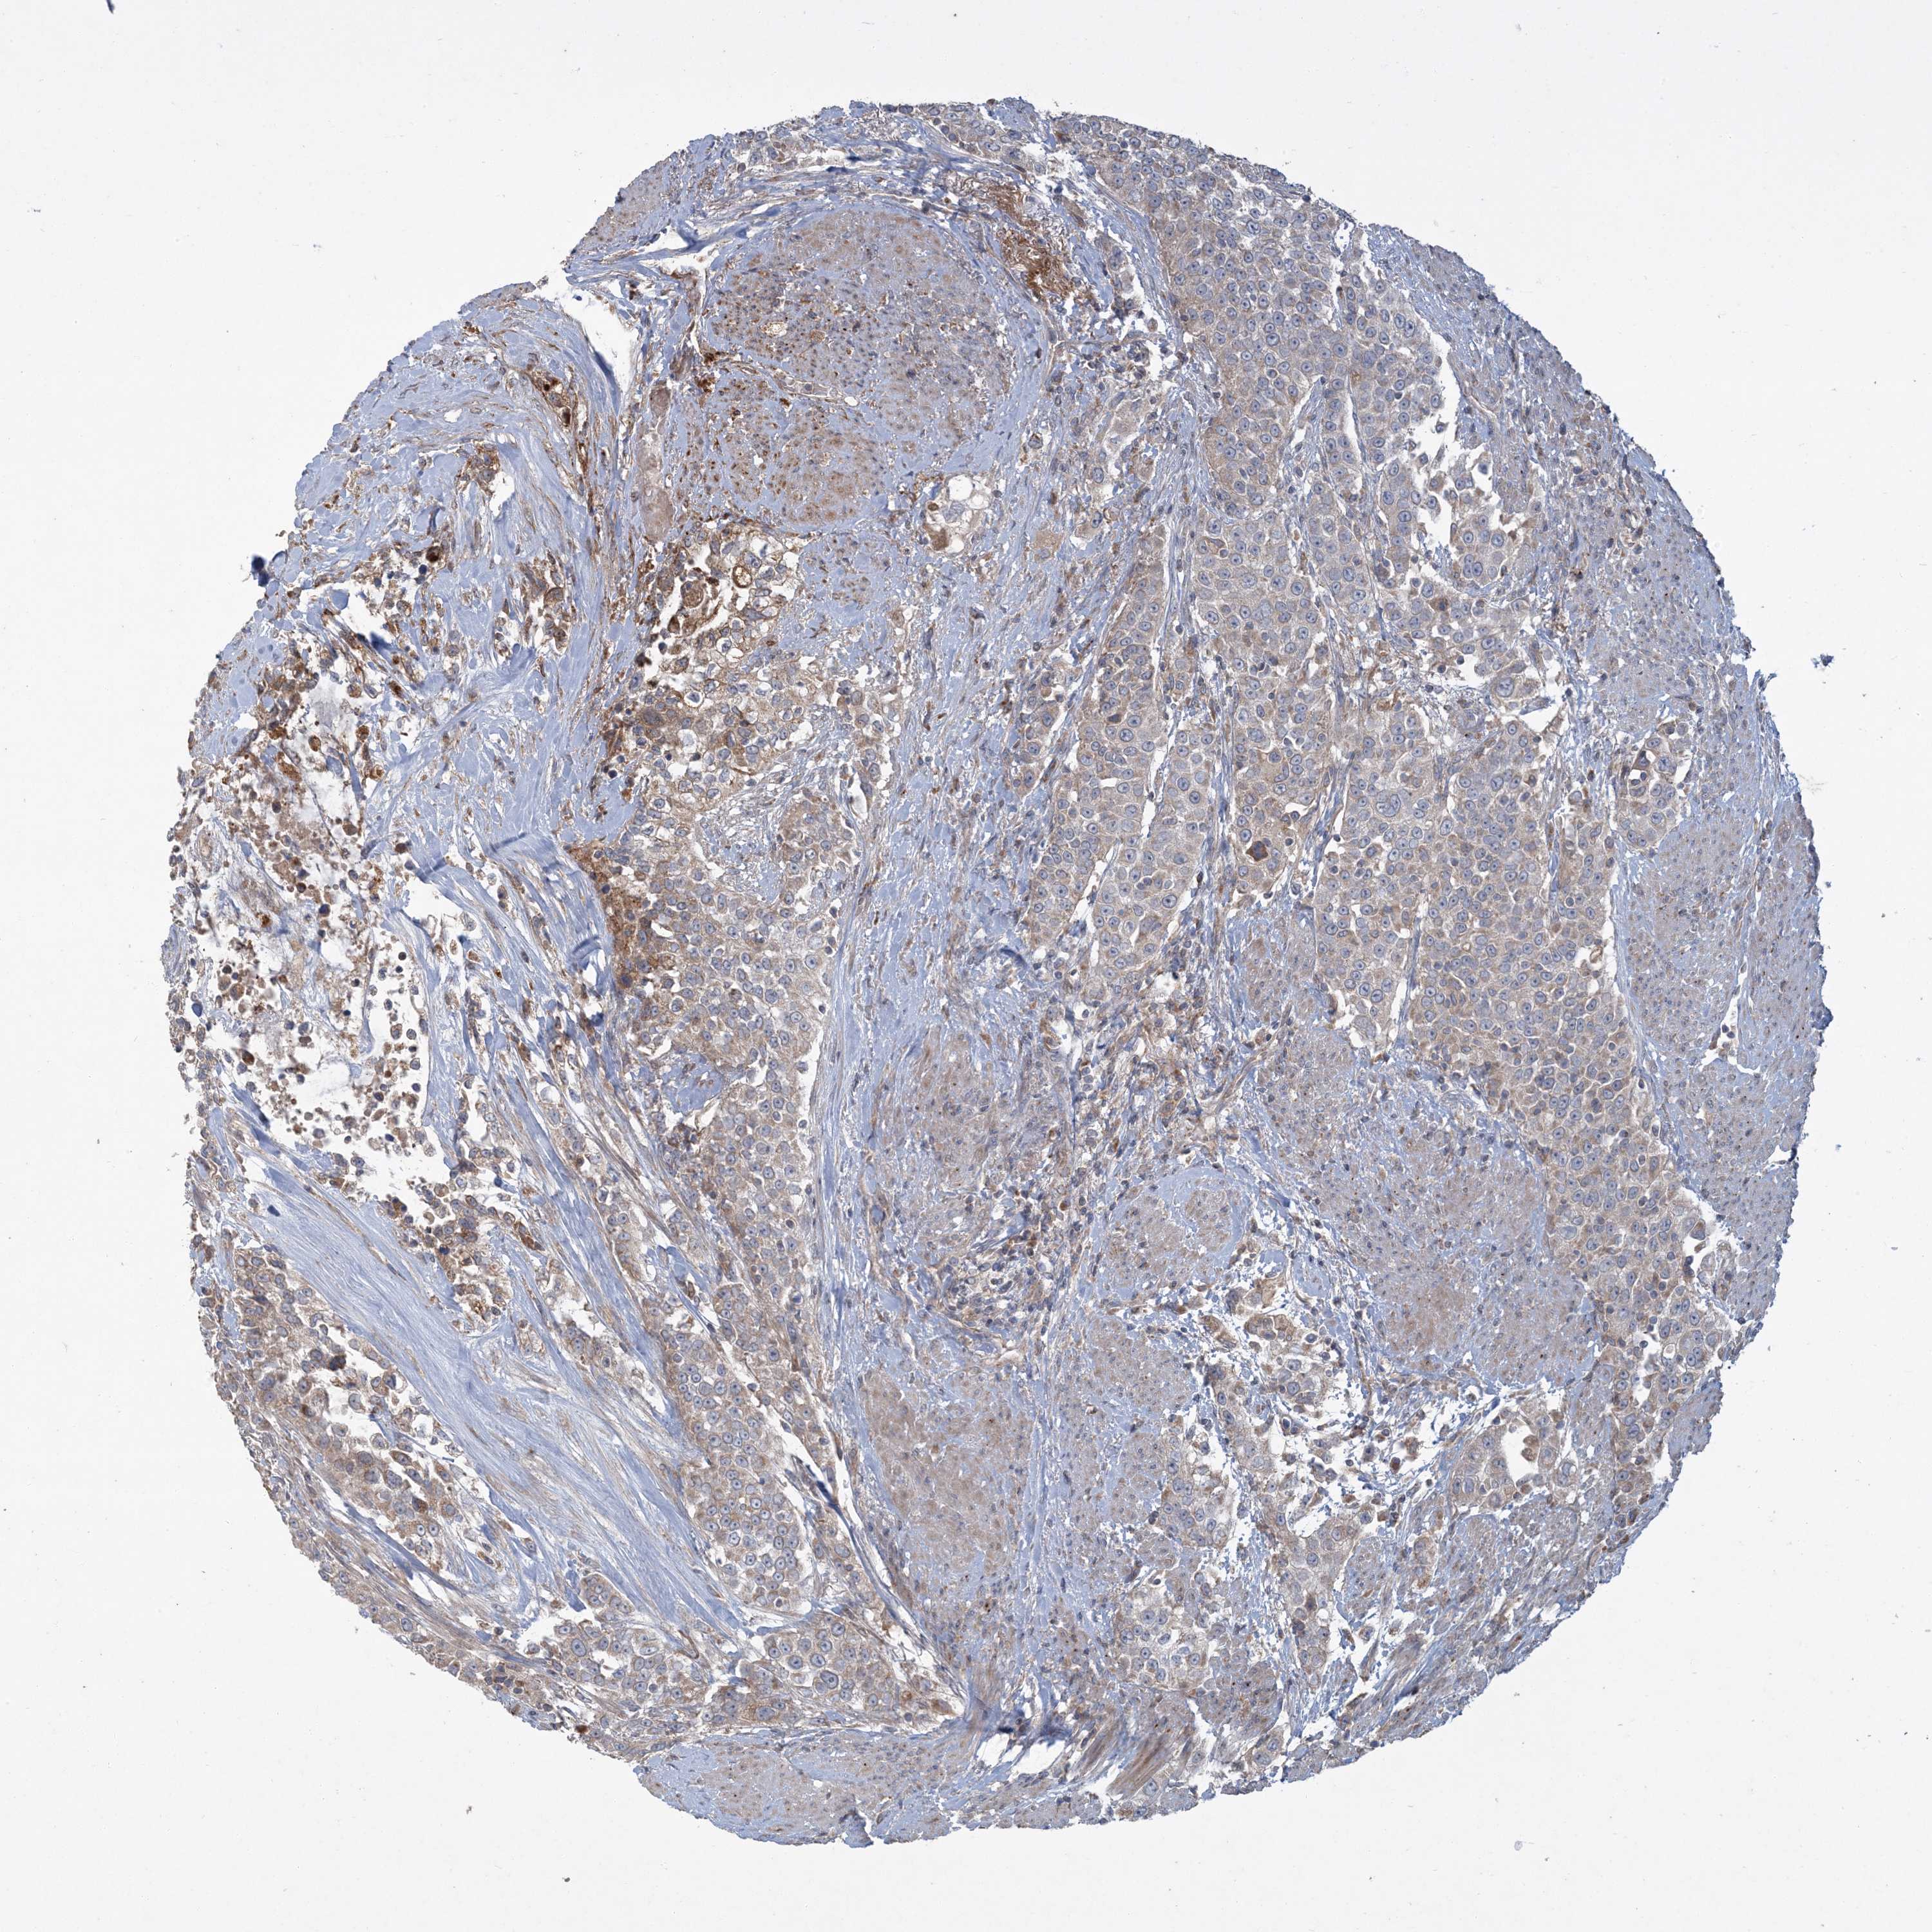

UROTHELIAL CANCER - Protein expressioni

A mouse-over function shows sample information and annotation data. Click on an image to view it in a full screen mode. Samples can be filtered based on level of antibody staining by selecting one or several of the following categories: high, medium, low and not detected. The assay and annotation is described here.

Antibody stainingi

Antibody staining in the annotated cell types in the current human tissue is reported as not detected, low, medium, or high, based on conventional immunohistochemistry profiling in selected tissues. This score is based on the combination of the staining intensity and fraction of stained cells.

Each image is clickable and will lead to virtual microscopy that enables deeper exploration of all samples and also displays staining intensity scores, fraction scores and subcellular localization as well as patient and tissue information for each sample.

Antibody HPA029143

Antibody CAB034164

Urothelial carcinoma, Low grade

Urothelial carcinoma, High grade